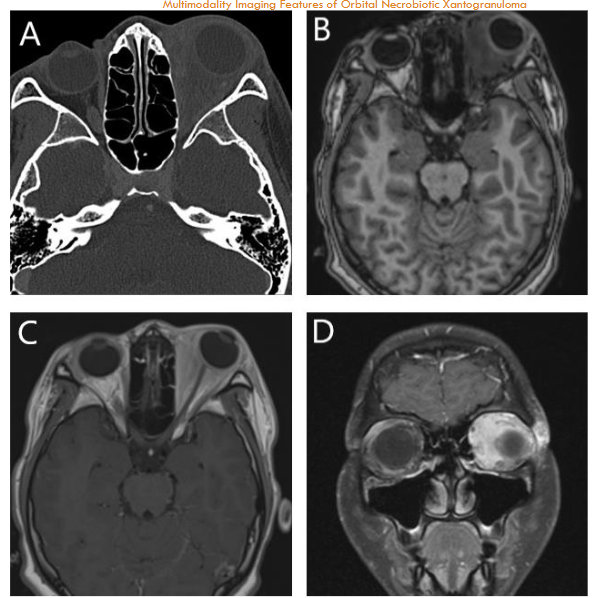

An orbital CT scan showed severe right orbital proptosis, right-sided pre- and post-septal soft tissue thickening with intraconal/retrobulbar space extension and diffuse thickening of the adjacent bone secondary to chronic inflammation without erosion. There was also diffuse paranasal sinus mucosal thickening.

Orbital MRI provided a clearer characterization of diffuse retro-orbital soft tissue thickening, involving the fat, extraocular muscles, and lacrimal glands, leading to pronounced right orbital proptosis and globe eversion. The right globe was flattened with optic nerve stretching. The retrobulbar mass extended posteriorly into the orbital apex without cavernous sinus involvement, and there was also further extension into the lateral face, affecting the temporalis muscle.